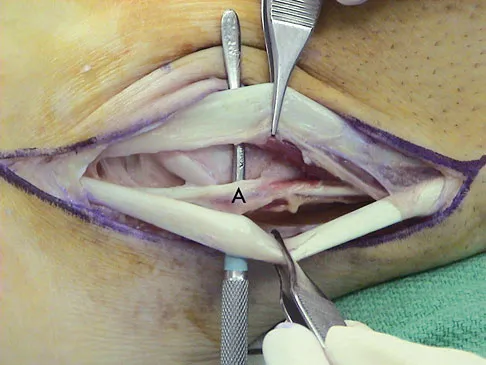

The primary function of structure "A" in Figure 29 is to limit

Explanation